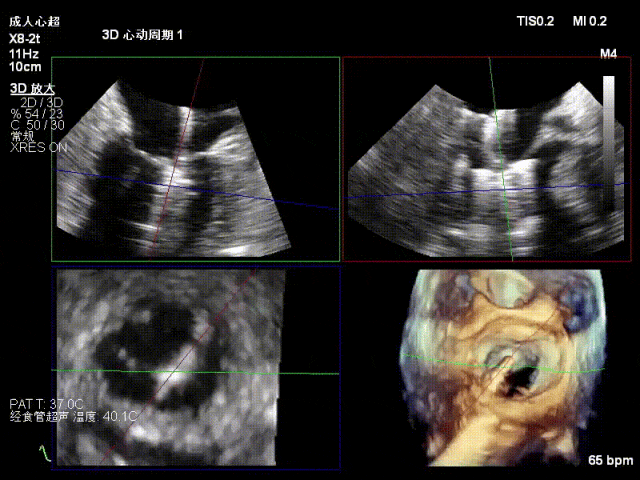

术中超声要点

退行性二尖瓣反流(DMR),P1/P2交界脱垂连枷(脱垂范围7mm,连枷间距4mm)

新分型:AAA型,MR 4+,VC:4×7mm

A1.5:20mm,P1.5:10mm,AP:30mm,MVA约3.8cm²